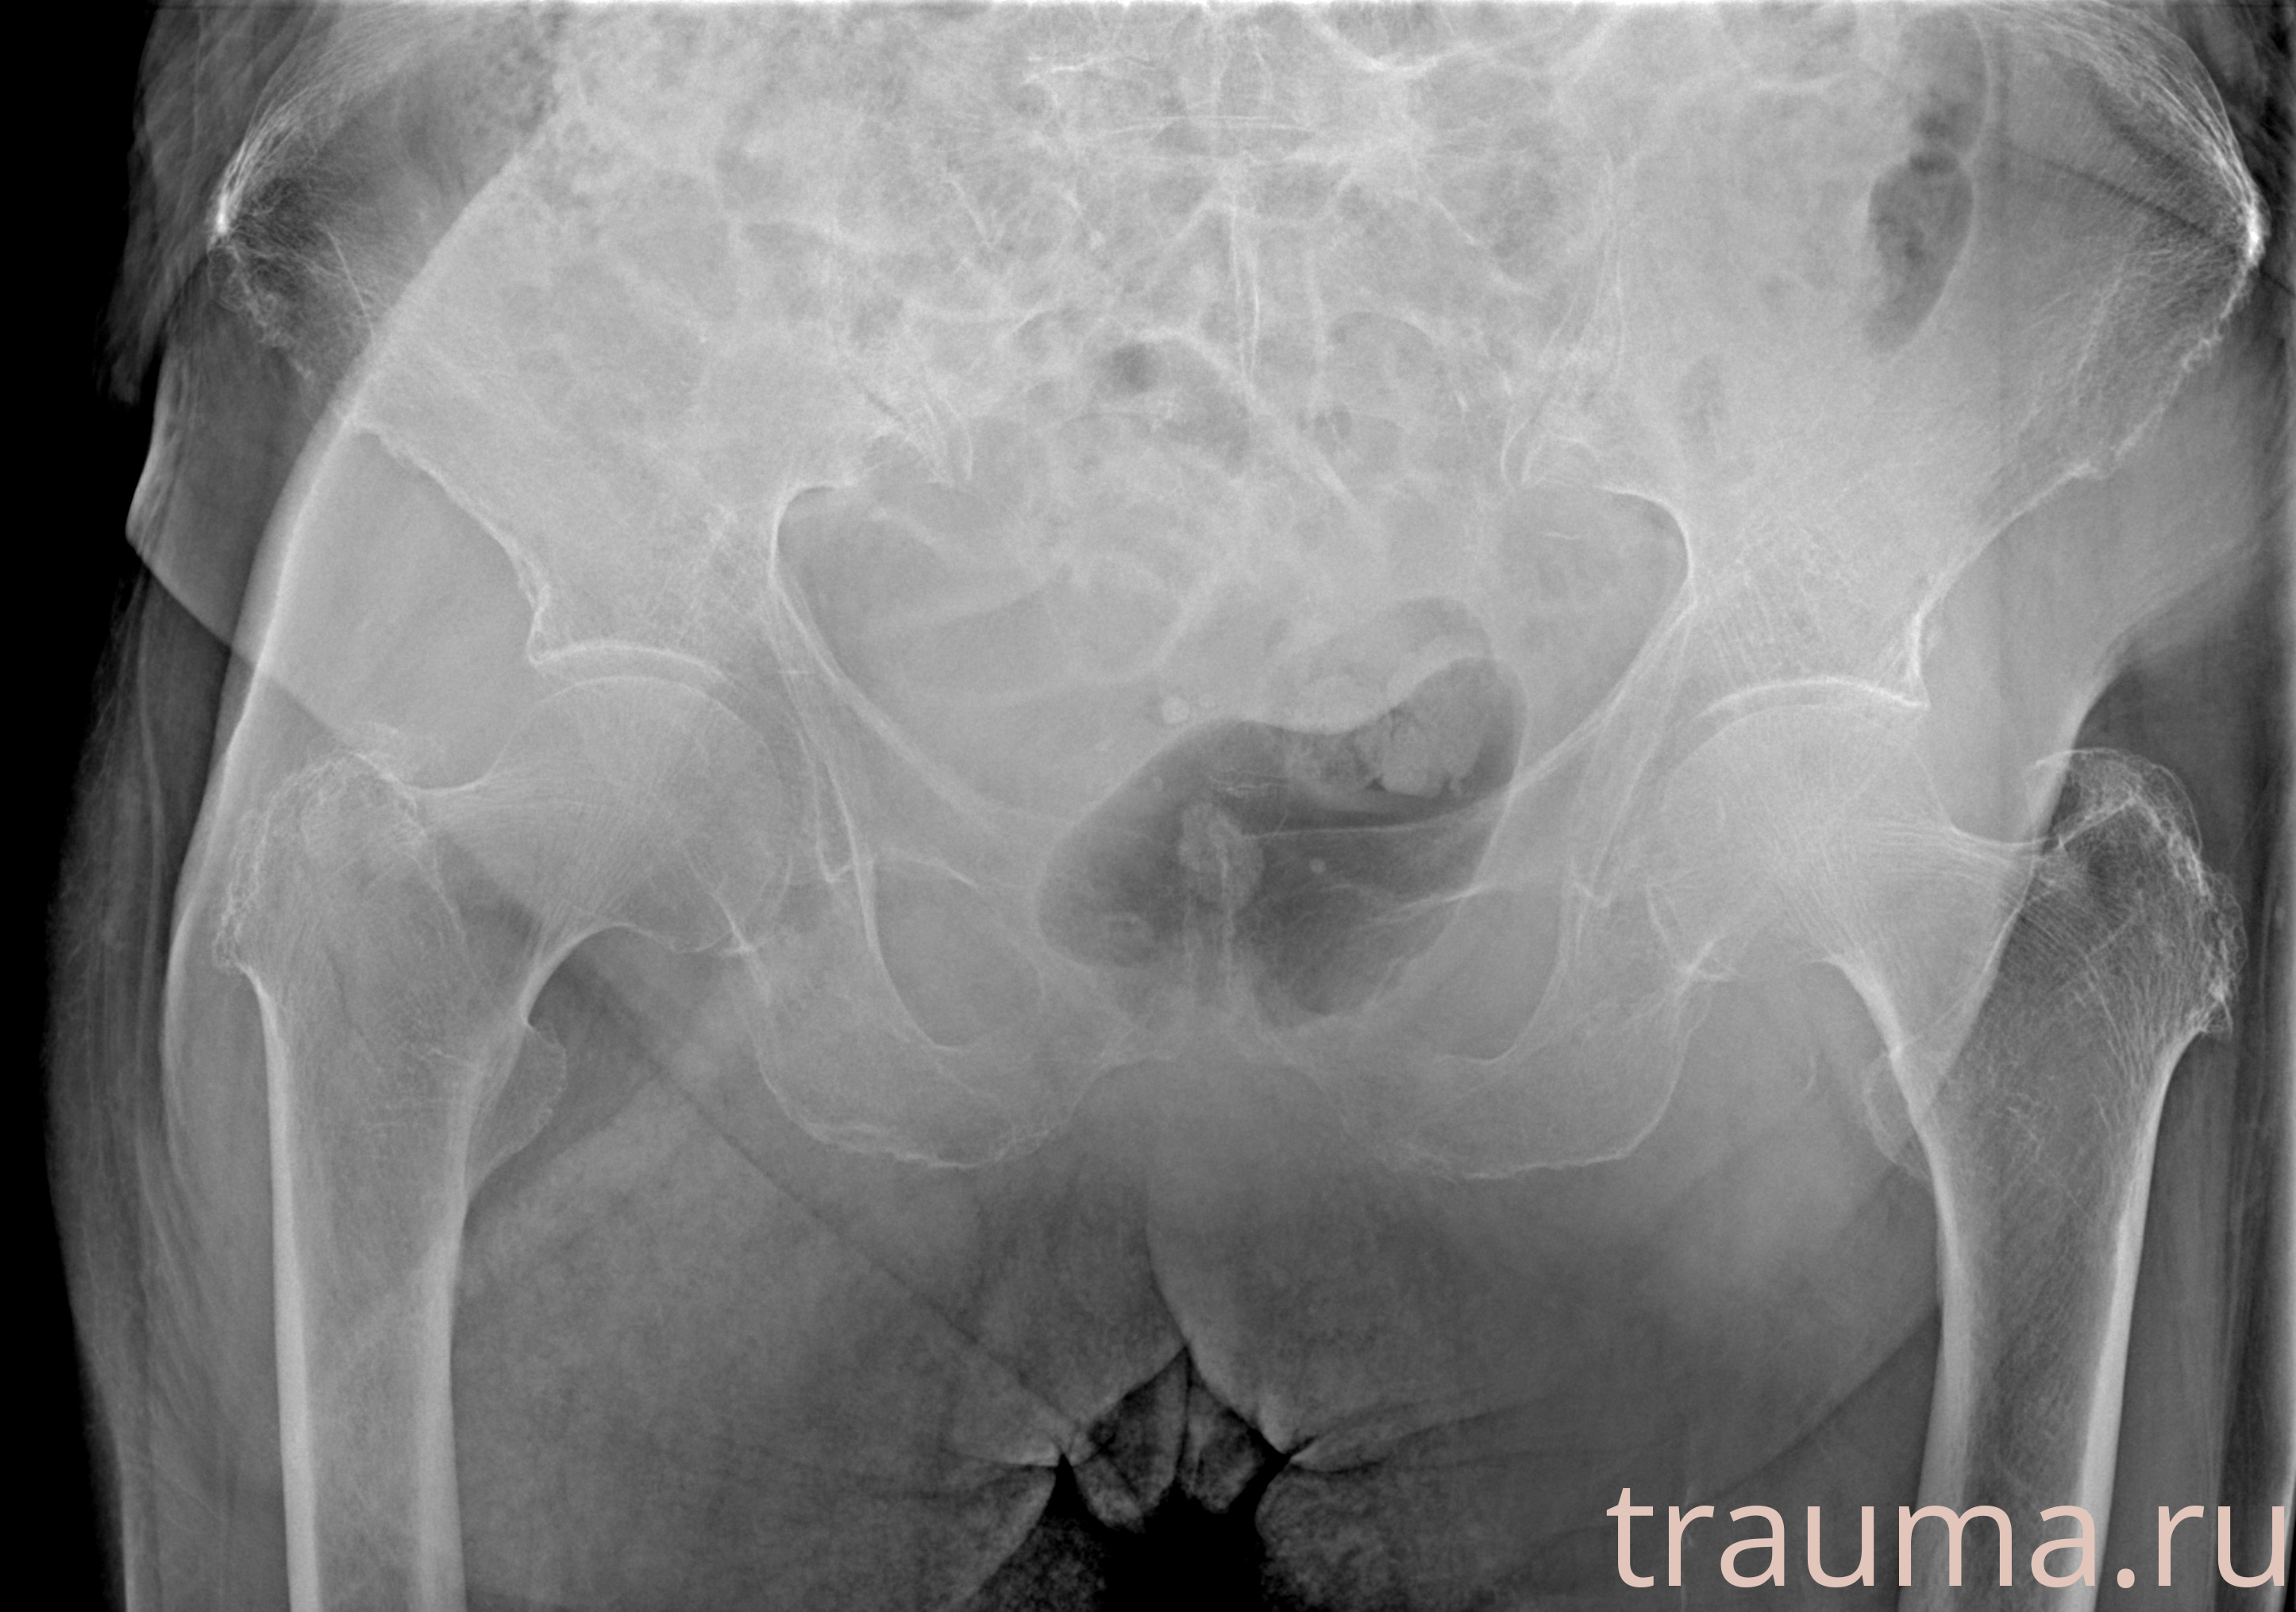

Рентгенограммы

Рентген на дому: по вашему адресу приезжает врач-рентгенолог, травматолог-ортопед с мобильным рентгеновским аппаратом, проводит диагностику травмы или заболевания, делает необходимые рентгенограммы, дает рекомендации по дальнейшему лечению. Получить качественные снимки в домашних условиях возможно благодаря уникальной методике, разработанной МосРентген Центром для института  Склифосовского